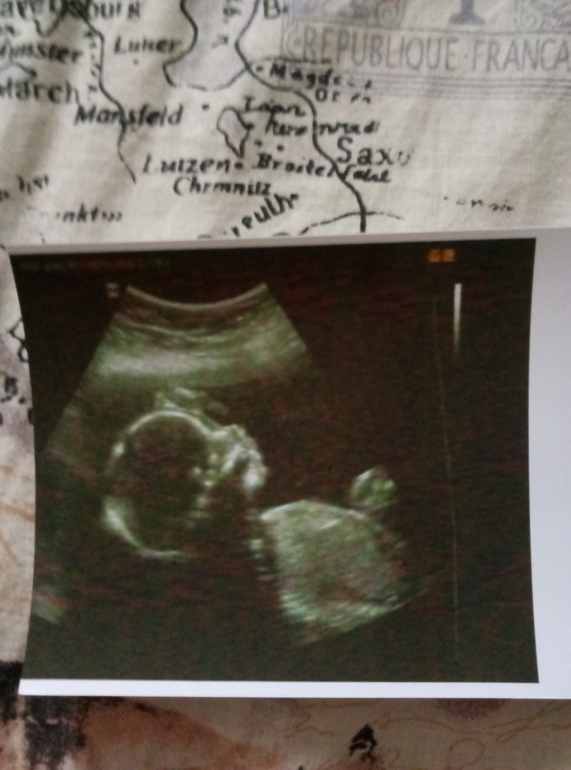

ЭкваторВсем привет! Вот и я долетела до этого дня!) Именно долетела, а не доползла) Так быстро пришел экватор, что я и не успела опомниться! только вроде писала в бб первый пост о 5-6 неделях, а уже экватор)) Далее многобуквенный пост, под кат что мы имеем. Вчера сдала кровь на гормон прогестерон,сдаю его систематически так как мои яичники сами не могут вырабатывать достаточную дозу прогестерона.Принимаю с 6недель утрожестан. Сейчас доза 300мг в сутки вагинально. Девочки, результат прекрасный! Значит мой гормончик сейчас 82,9нг/мл при норме для 2го триместра 25,6-89,4. Тоесть я практически у верхней границы!!Ура! 🎉🎈😜Начинала я с отметки 23.21... Вот так. Рада до безумия) Была вчера на Узи. Мишутка подрос!! Такой милый и шладкий 😍Ручкой махал, трогал головку, дергал себя за ножку, за ушко, тащил палец в рот и пускал пузыри. Весим мы 292грамма.Опережаем как обычно на 2-3дня)) По здоровью у нас всё хорошо. Сердечко стучит 154удара. Плацента моя поднялась, была низковата. Сейчас сказали в пределах нормы, на 40мм выше внутреннего зева. Рубец после кесарево тоже в хорошем состоянии 6,8мм. Шейка! Подшита на всякий случай мерселеновой лентой тоже ведет себя хорошо) 39мм,все закрыто) Тонус отсутствует) 😍😍😍🎉🎈Вот такое прекрасное узи,которое меня безумно обрадовало) У узиста было др, все её поздравляли и у нее было хорошее настроение и я даже смогла выпросить фото малыша))) обычно она не оч любит такое делать...Вот мой Мишутка

на фото там где малыш не трогает себя за голову видно пузыри в районе ушка) Чувствую себя хорошо) Мишутка шевелится и здоровается со мной)) Купили коляску. Сынок лежит больше справа. Узист сказала, что справа головка) Но еще такой срок когда малышу много места, поэтому он верится так как пожелает) Вот такие мы были сутра когда поворачивались